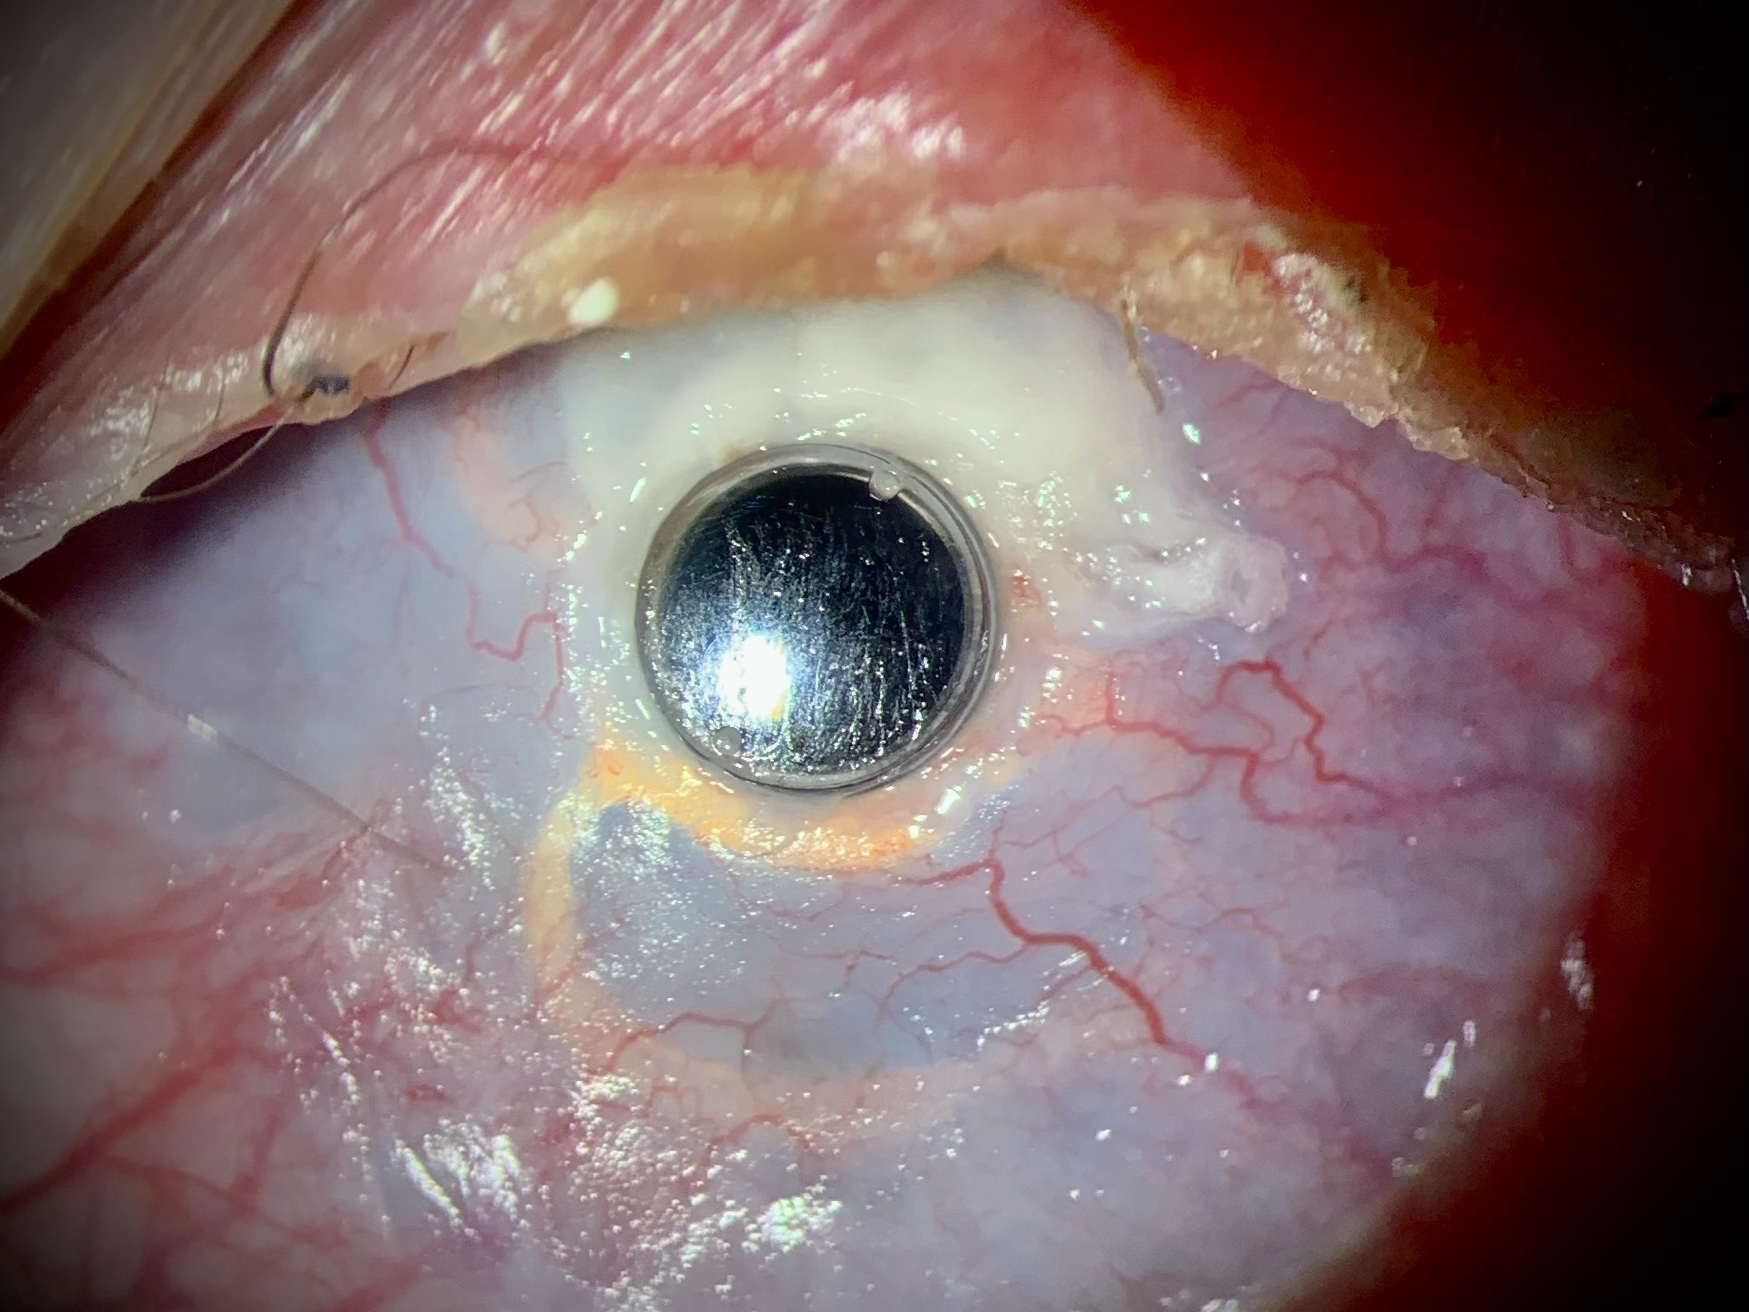

At discharge, the left fundus was ophthalmoscoped. The optic disc was pale and well-defined with a cup-to-disc ratio of 0.4. There were no focal macular or peripheral gross abnormalities. Optical coherence tomography of the macula and optic disc showed no structural changes in the examined areas of the fundus (Fig. 5).

Fig. 5. Optical coherence tomography of macular area and optic nerve head of the left eye

Рис. 5. Оптическая когерентная томография макулярной зоны и диска зрительного нерва левого глаза

Six months after surgery, the uncorrected visual acuity of the left eye remained the same (0.2), and the position of the supporting element and the optical cylinder of the keratoprosthesis did not change (Fig. 6).

Fig. 6. Biomicroscopic appearance six months after the second stage of keratoprosthetics

Рис. 6. Биомикроскопическая картина через полгода после второго этапа кератопротезирования